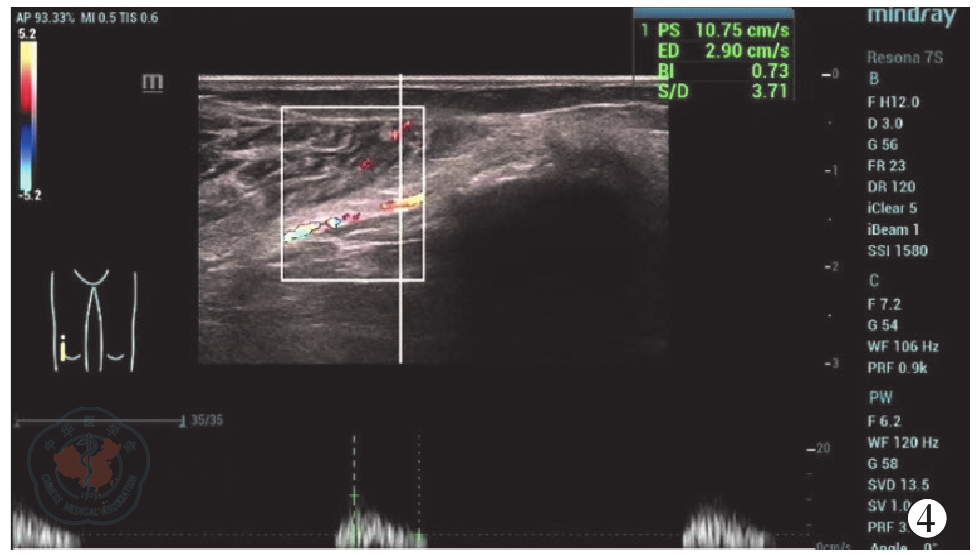

Wu J, Li Y, Zhang X, et al. Assessment of blood flow around the knee joint in patients with knee osteoarthritis by color Doppler ultrasound[J/OL]. Eur J Radiol, 2023, 166: 111005. DOI: 10.1016/j.ejrad.2023.111005.

|